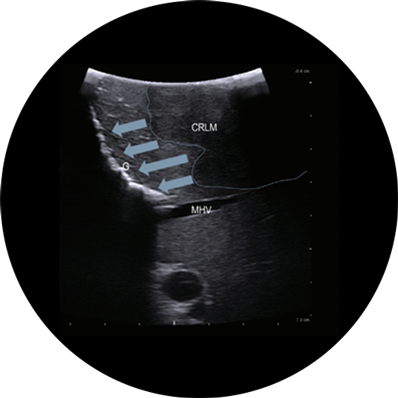

Gallbladder adenocarcinoma, visualized with Laparoscopic Transducer

The Assurance You Need for Minimally Invasive Procedures

Intraoperative ultrasound can assist in identifying 10-25% additional

hepatic lesions than with preoperative imaging alone1,2